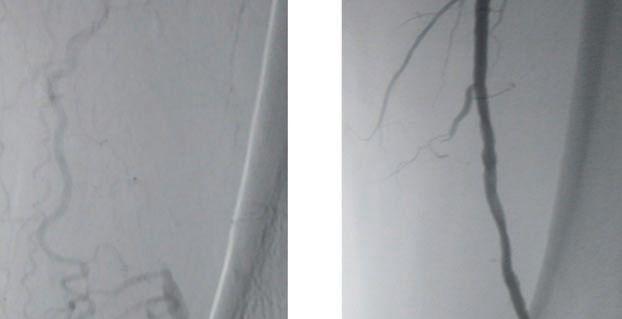

Atherectemy And Angioplasty

This patient suffered from peripheral artery disease of the thigh. Drs. Upadya and Yelamanchi used atherectomy and angioplasty to successfully treat this patient. The quality of their work helped improve the patient’s circulation and decrease pain. They’ve enjoyed many successful outcomes treating peripheral artery disease.